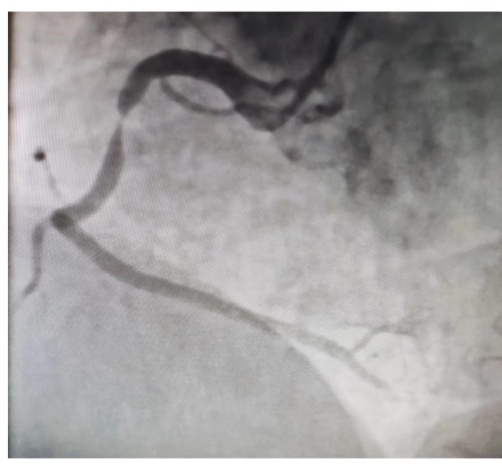

该患者右冠状动脉中段严重狭窄引起患者冠脉缺血,稍活动则诱发胸闷胸痛,冠状动脉造影显示患者右冠状动脉中段狭窄90%,冠状动脉支架植入术后,右冠状动脉残余狭窄0%,患者步行回病房,未再发作胸闷胸痛等症状。(冠脉造影见下图)

术前